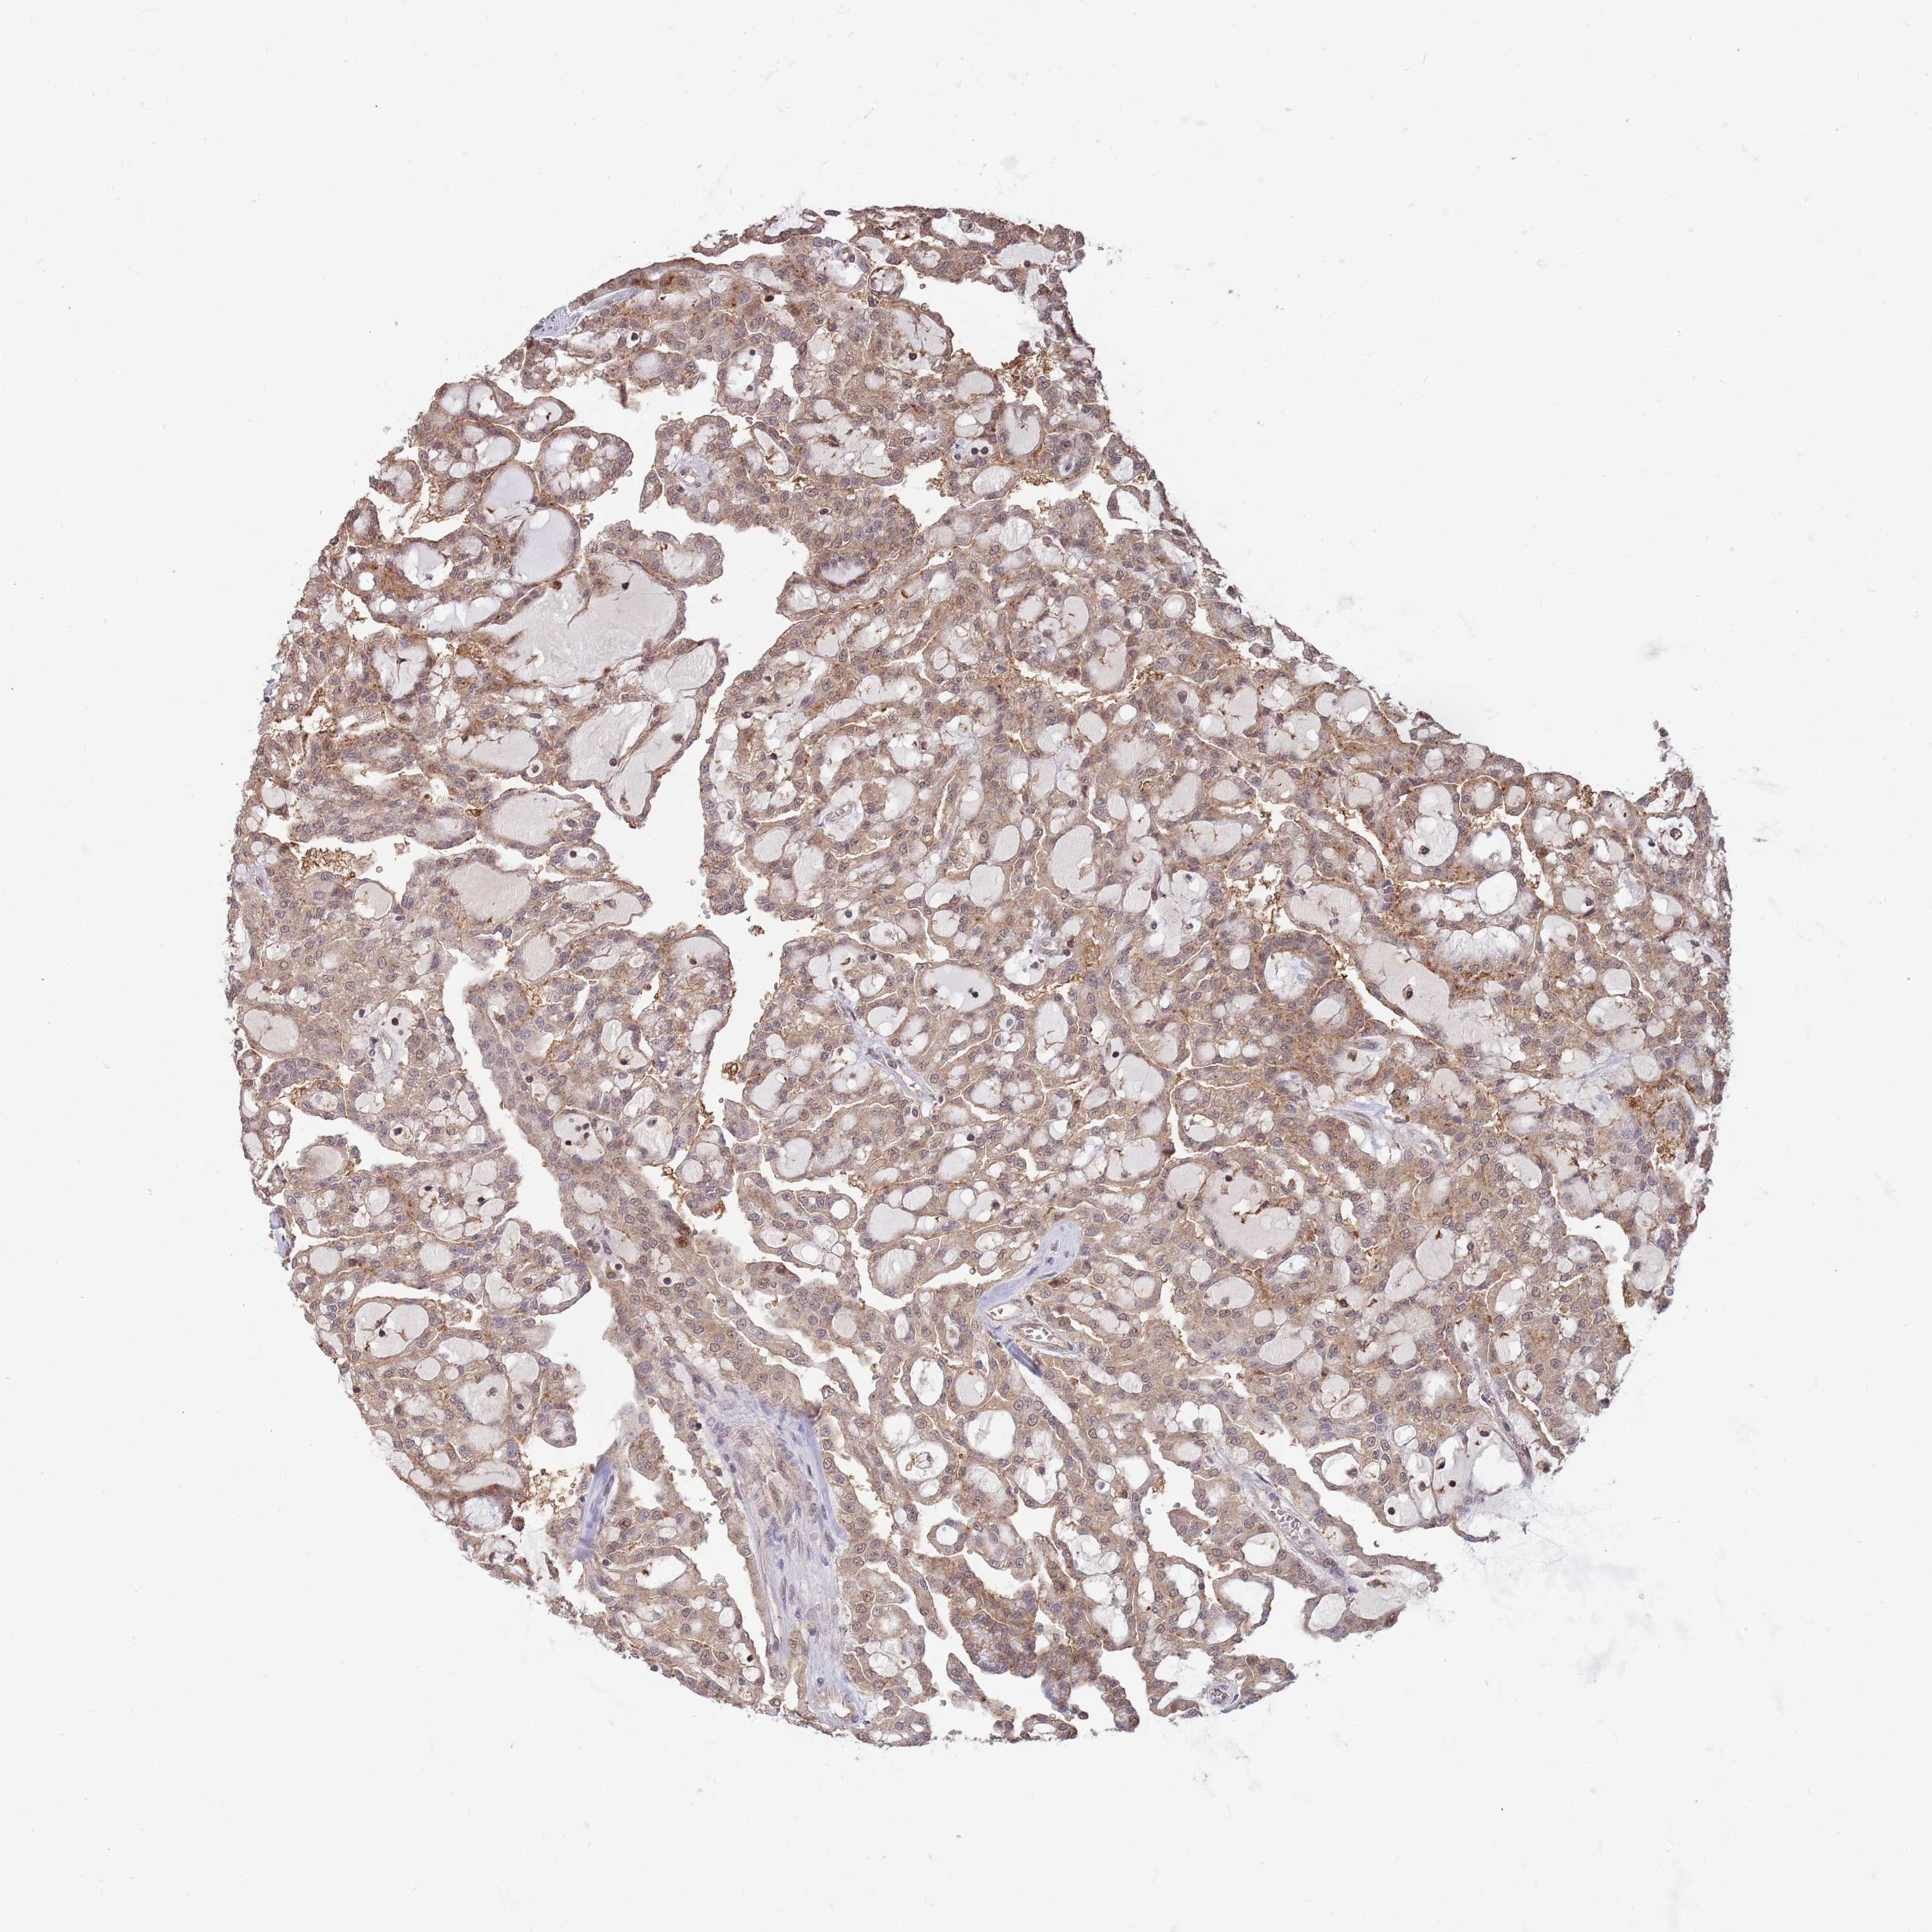

SALL1 is validated prognostic, high expression is favorable in Kidney Renal Clear Cell Carcinoma (TCGA)

Best expression cut offi

When clicking on this number, the vertical dashed line indicating cut-off, the interactive survival plot, and the Kaplan-Meier curve will be adjusted to show results based on the best expression cut-off.

: 20.12

TCGA RNA samplesi

RNA-seq data is reported as average FPKM (number Fragments Per Kilobase of exon per Million reads), generated by the The Cancer Genome Atlas (TCGA) .

Normal distribution across the dataset is visualized with box plots, shown as median and 25th and 75th percentiles. Points are displayed as outliers if they are above or below 1.5 times the interquartile range. FPKM values of the individual samples are presented next to the box plot.

Average pTPM 25.9

Number of samples 521